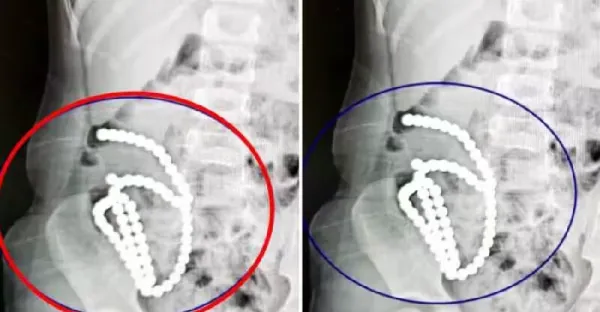

4歲妹照X光驚見「肚子整串白珠珠」媽證實哥哥在玩!醫嘆:一輩子毀了…